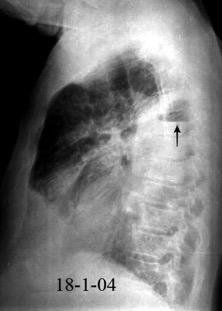

Neumonía a neumococos base izda. con derrame que aumenta.

Broncograma en lateral y en US.

(36-66% en ingresados)